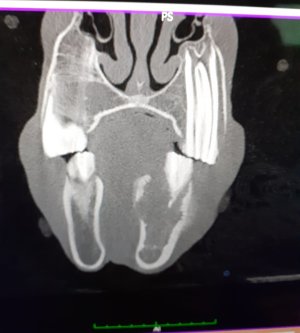

2 screws. And no fancy smancy hi tech kit either - a DeWalt drill, some major heavy duty screws from screwfix and some saline. A few months rest then back into training. The horse ran for a few more years and won a couple as well after this.

• Screenshot_20230724-180648_Gallery.jpg

Screenshot_20230724-180648_Gallery.jpg

67.7 KB · Views: 300